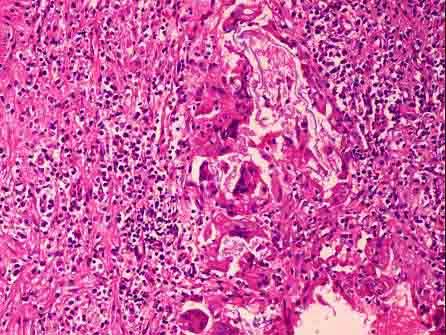

如图,背部皮下肿块切除,病理诊断为“表皮囊肿”,镜下见真皮内异位鳞状上皮角化,形成囊肿,囊肿部分破裂,巨噬细胞等围绕形成结节(如图所示)。此结节病变应称 ...

问题 如图,背部皮下肿块切除,病理诊断为“表皮囊肿”,镜下见真皮内异位鳞状上皮角化,形成囊肿,囊肿部分破裂,巨噬细胞等围绕形成结节(如图所示)。此结节病变应称 ( )

选项 A.脓肿 B.结核结节 C.异物肉芽肿 D.机化 E.钙化

答案 C